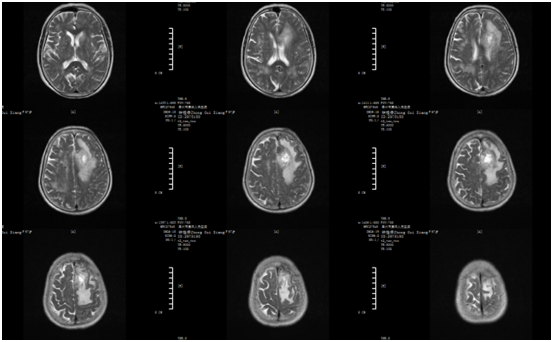

圖片來源 | 神外一區(qū) & 網(wǎng)絡(luò)